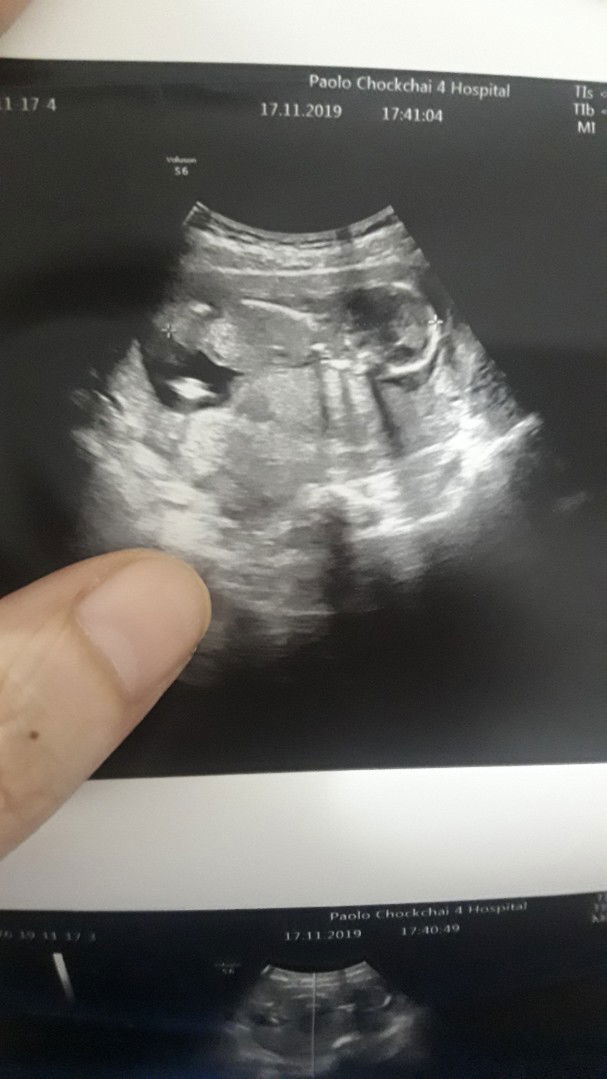

15 สัปดาห์ 4 วันแล้วครับ ???